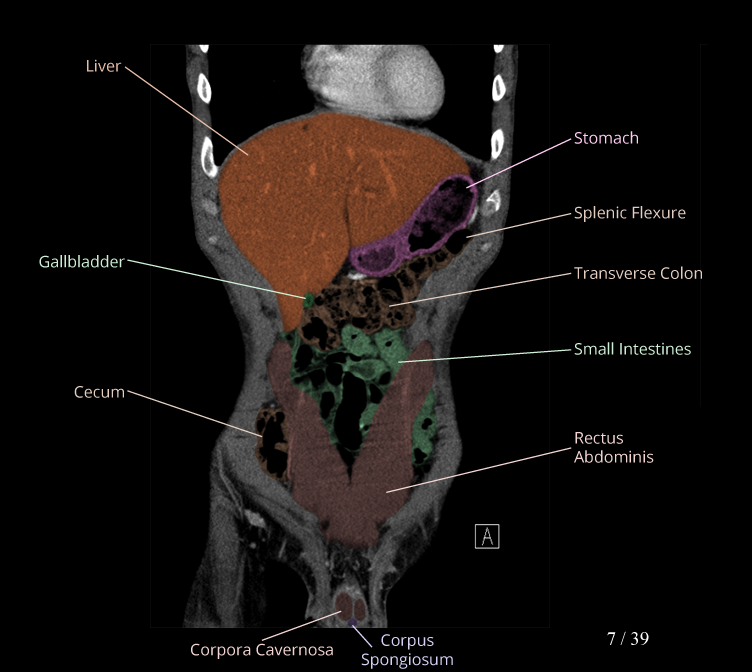

Body

Covers abdominal CT anatomy.